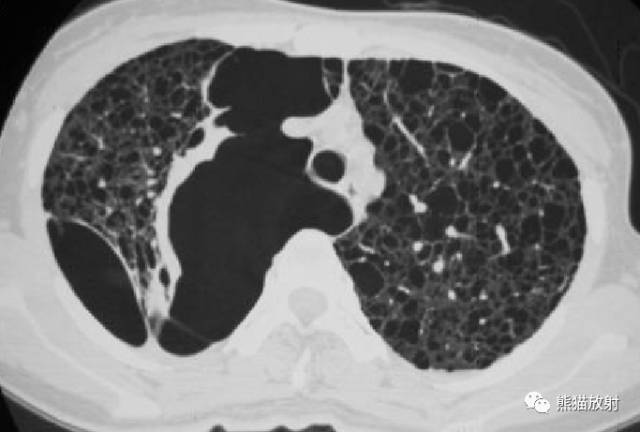

【影像表现】

胸部CT:双肺弥漫分布大小不等薄壁囊状空气密度影,且胸膜下区低密度影明显较其他部位大,周围见索条状高密度影。阴影之间肺组织基本正常。

②双肺弥漫分布囊状空气密度影,有薄壁,小叶中央动脉位于病灶边缘部分。此有别于小叶中央型肺气肿。